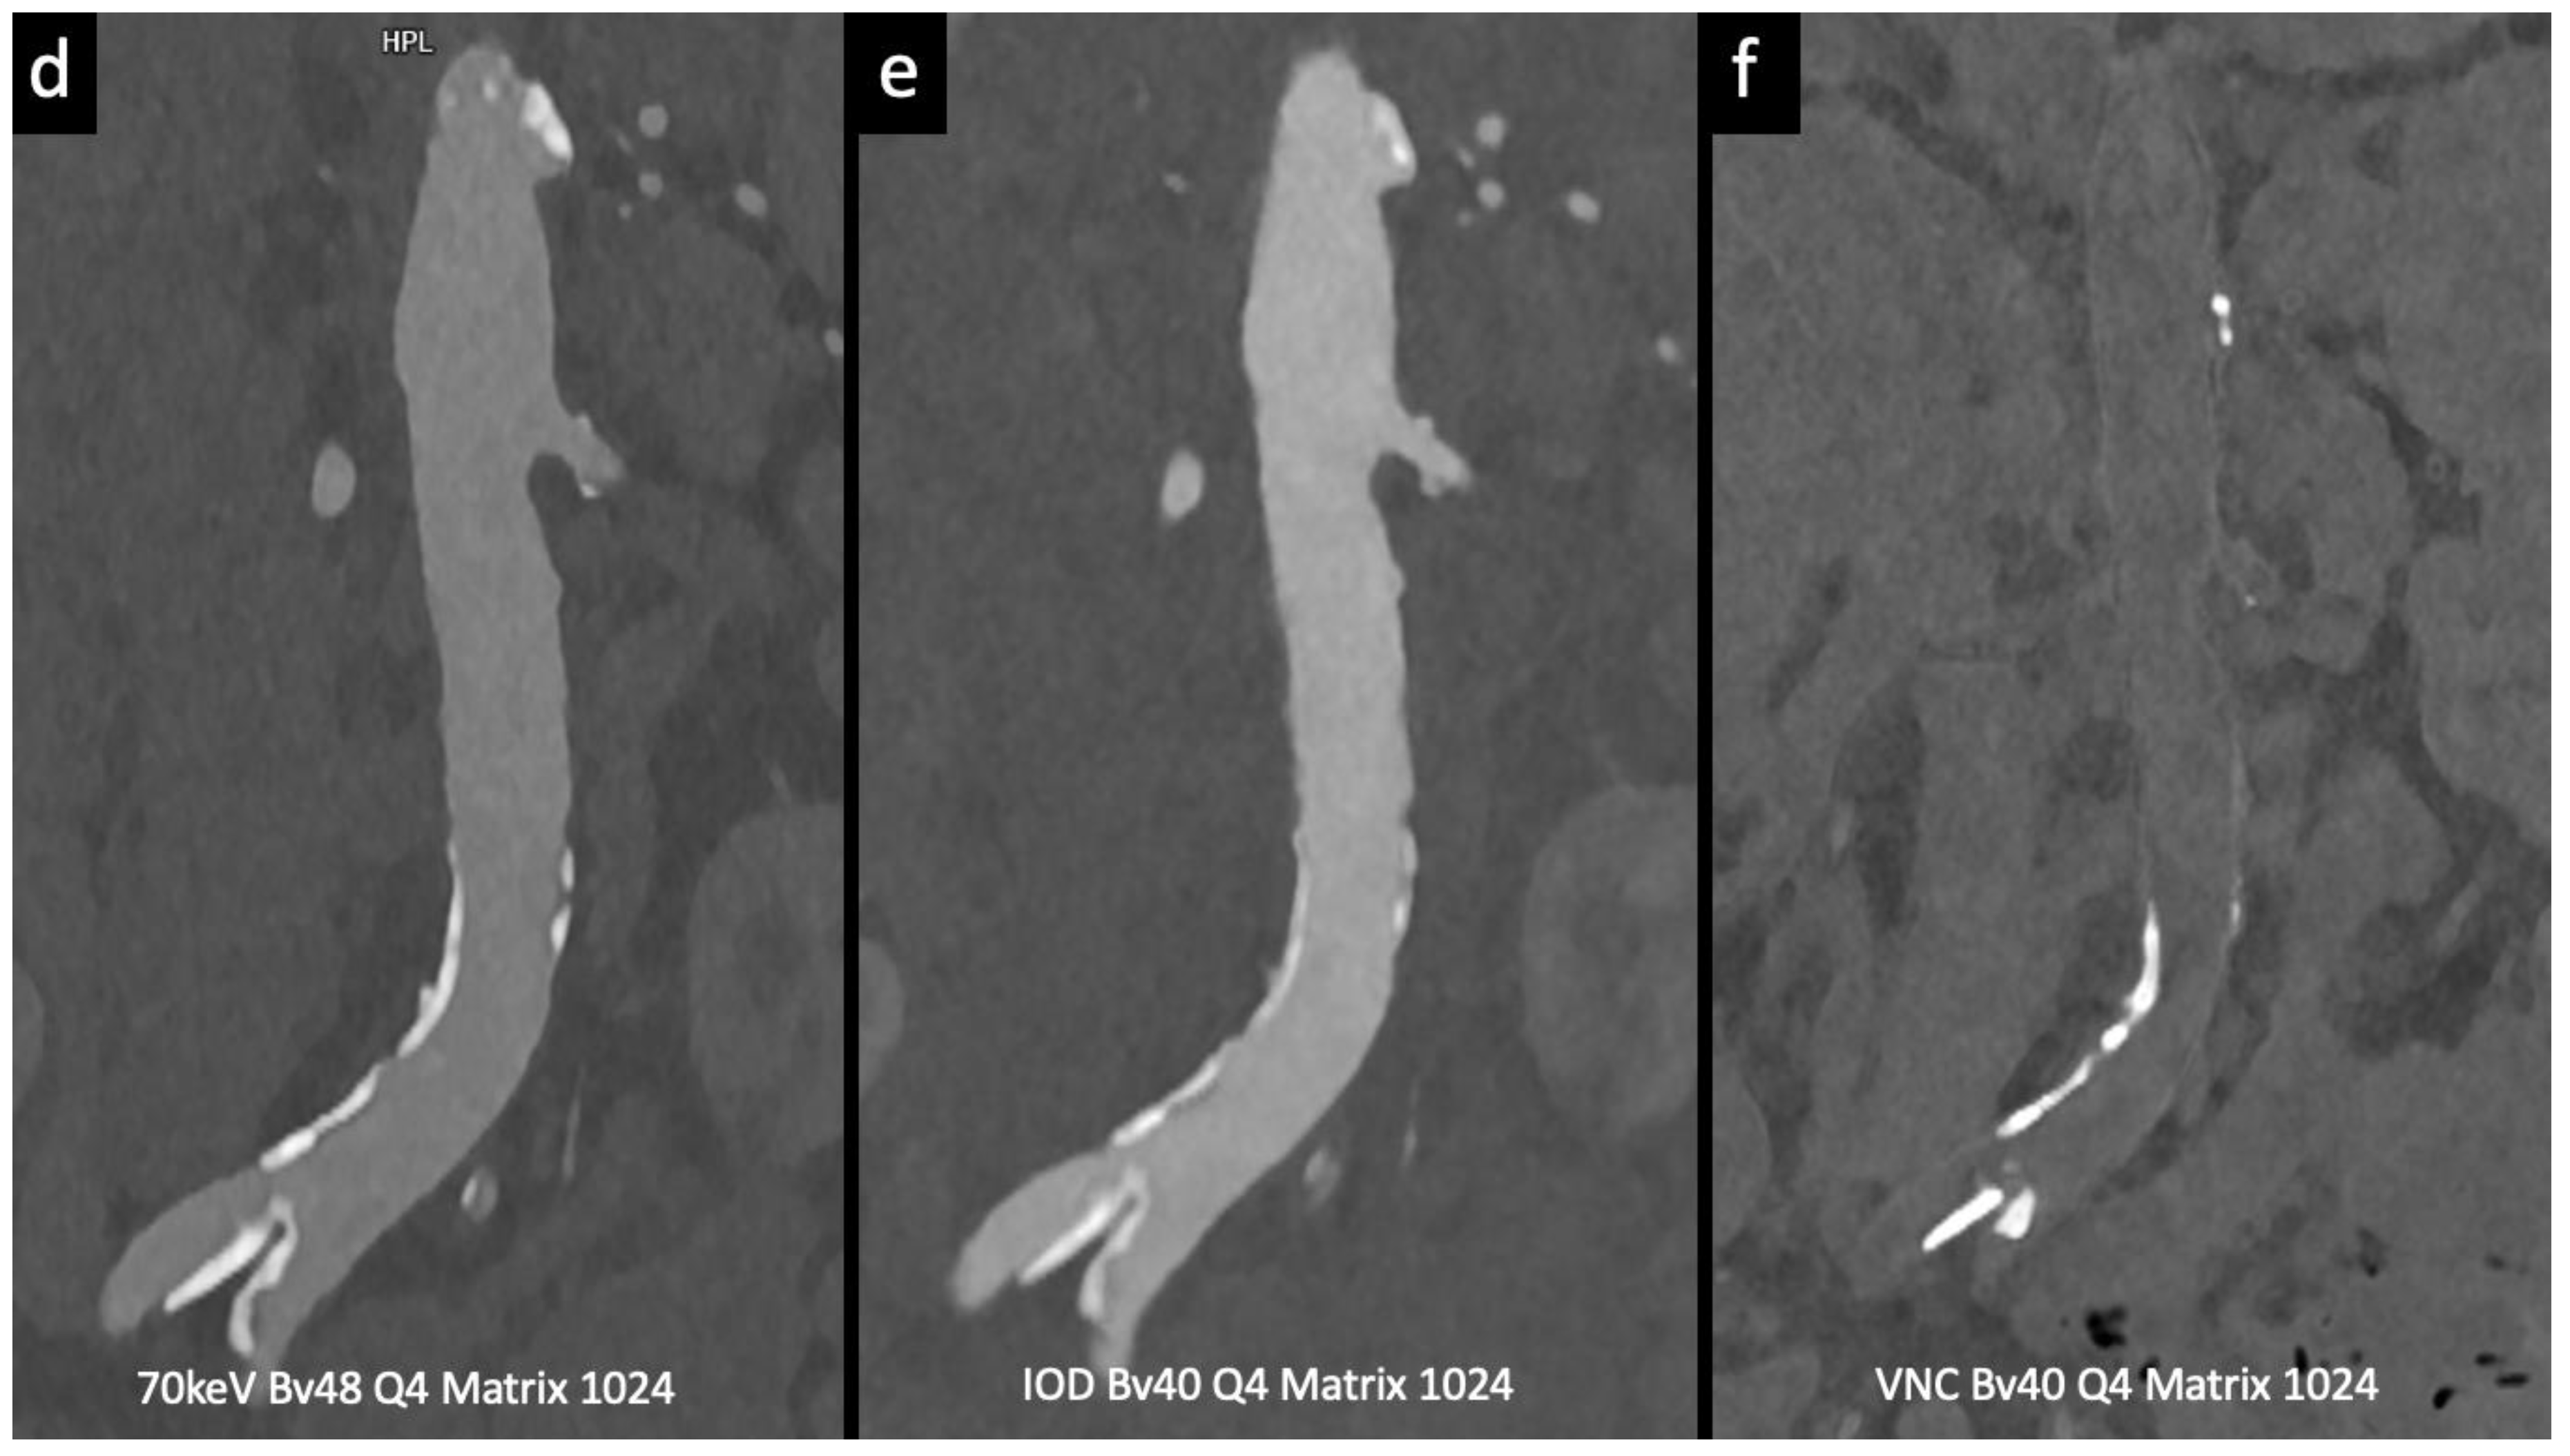

- Virtual monoenergetic images at optimal energy levels improve contrast-to-noise ratios, resulting in higher image quality and reduced contrast-related risk.

- Rau, S.; Soschynski, M.; Schlett, C. L.; Hagar, M. T. Spectral Aortoiliac Photon-Counting CT Angiography with Minimal Quantity of Contrast Agent. Radiol Case Rep 2023, 18 (6), 2180–2182. [CrossRef]

- Euler, A.; Higashigaito, K.; Mergen, V.; Sartoretti, T.; Zanini, B.; Schmidt, B.; Flohr, T. G.; Ulzheimer, S.; Eberhard, M.; Alkadhi, H. High-Pitch Photon-Counting Detector Computed Tomography Angiography of the Aorta. Invest Radiol 2022, 57 (2), 115–121. [CrossRef]

Rau et al. Radiology Case Reports 2023[10] |

Case report (follow-up imaging of AAA) |

|